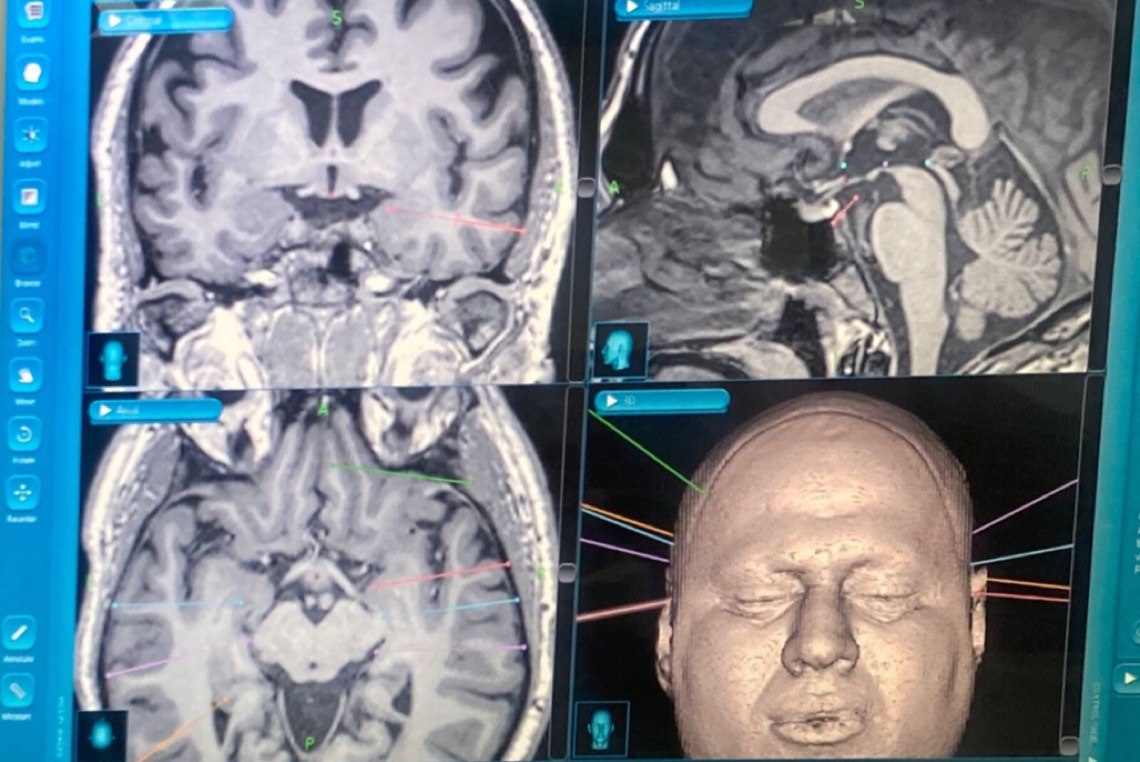

وبين الدكتور زياد الثاني أن هذا الأسلوب الجراحي SEEG يتطلب بعض الترتيبات المسبقة من خلال تحديد أماكن زراعة الحساسات عن طريق التخطيط الكهربي للدماغ وأشعة الرنين المغناطيسي، وتحديد مسارات زراعة الحساسات بدقه في الدماغ باستخدام الجهاز الملاحي.